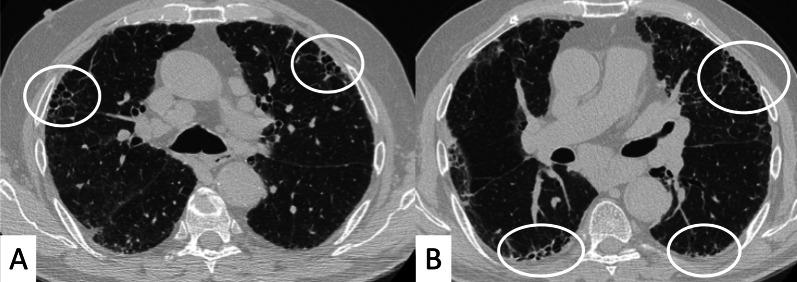

Connective tissue diseases (CTDs) include a spectrum of disorders that affect the connective tissue of the human body; they include autoimmune disorders characterized by immune-mediated chronic inflammation and the development of fibrosis. Lung involvement can be misdiagnosed, since pulmonary alterations preceded osteo-articular manifestations only in 20% of cases and they have no clear clinical findings in the early phases. All pulmonary structures may be interested: pulmonary interstitium, airways, pleura and respiratory muscles. Among these autoimmune disorders, rheumatoid arthritis (RA) is characterized by usual interstitial pneumonia (UIP), pulmonary nodules and airway disease with air-trapping, whereas non-specific interstitial pneumonia (NSIP), pulmonary hypertension and esophageal dilatation are frequently revealed in systemic sclerosis (SSc). NSIP and organizing pneumonia (OP) may be found in patients having polymyositis (PM) and dermatomyositis (DM); in some cases, perilobular consolidations and reverse halo-sign areas may be observed. Systemic lupus erythematosus (SLE) is characterized by serositis, acute lupus pneumonitis and alveolar hemorrhage. In the Sjögren syndrome (SS), the most frequent pattern encountered on HRCT images is represented by NSIP; UIP and lymphocytic interstitial pneumonia (LIP) are reported with a lower frequency. Finally, fibrotic NSIP may be the interstitial disease observed in patients having mixed connective tissue diseases (MCTD). This pictorial review therefore aims to provide clinical features and imaging findings associated with autoimmune CTDs, in order to help radiologists, pneumologists and rheumatologists in their diagnoses and management.

结缔组织病(CTDs)包括一系列影响人体结缔组织的疾病;它们包括以免疫介导的慢性炎症和纤维化发展为特征的自身免疫性疾病。肺部受累可能会被误诊,因为肺部改变仅在20%的病例中先于骨关节炎表现出现,且在早期阶段没有明确的临床发现。所有肺部结构都可能受累:肺间质、气道、胸膜和呼吸肌。在这些自身免疫性疾病中,类风湿关节炎(RA)的特征是普通型间质性肺炎(UIP)、肺结节和伴有空气潴留的气道疾病,而系统性硬化症(SSc)常表现为非特异性间质性肺炎(NSIP)、肺动脉高压和食管扩张。NSIP和机化性肺炎(OP)可见于多发性肌炎(PM)和皮肌炎(DM)患者;在某些情况下,可观察到小叶周围实变和反晕征区域。系统性红斑狼疮(SLE)的特征是浆膜炎、急性狼疮性肺炎和肺泡出血。在干燥综合征(SS)中,HRCT图像上最常见的表现是NSIP;UIP和淋巴细胞间质性肺炎(LIP)的报道频率较低。最后,纤维化NSIP可能是混合性结缔组织病(MCTD)患者中观察到的间质性疾病。因此,本图像综述旨在提供与自身免疫性CTDs相关的临床特征和影像学表现,以帮助放射科医生、呼吸科医生和风湿病科医生进行诊断和管理。